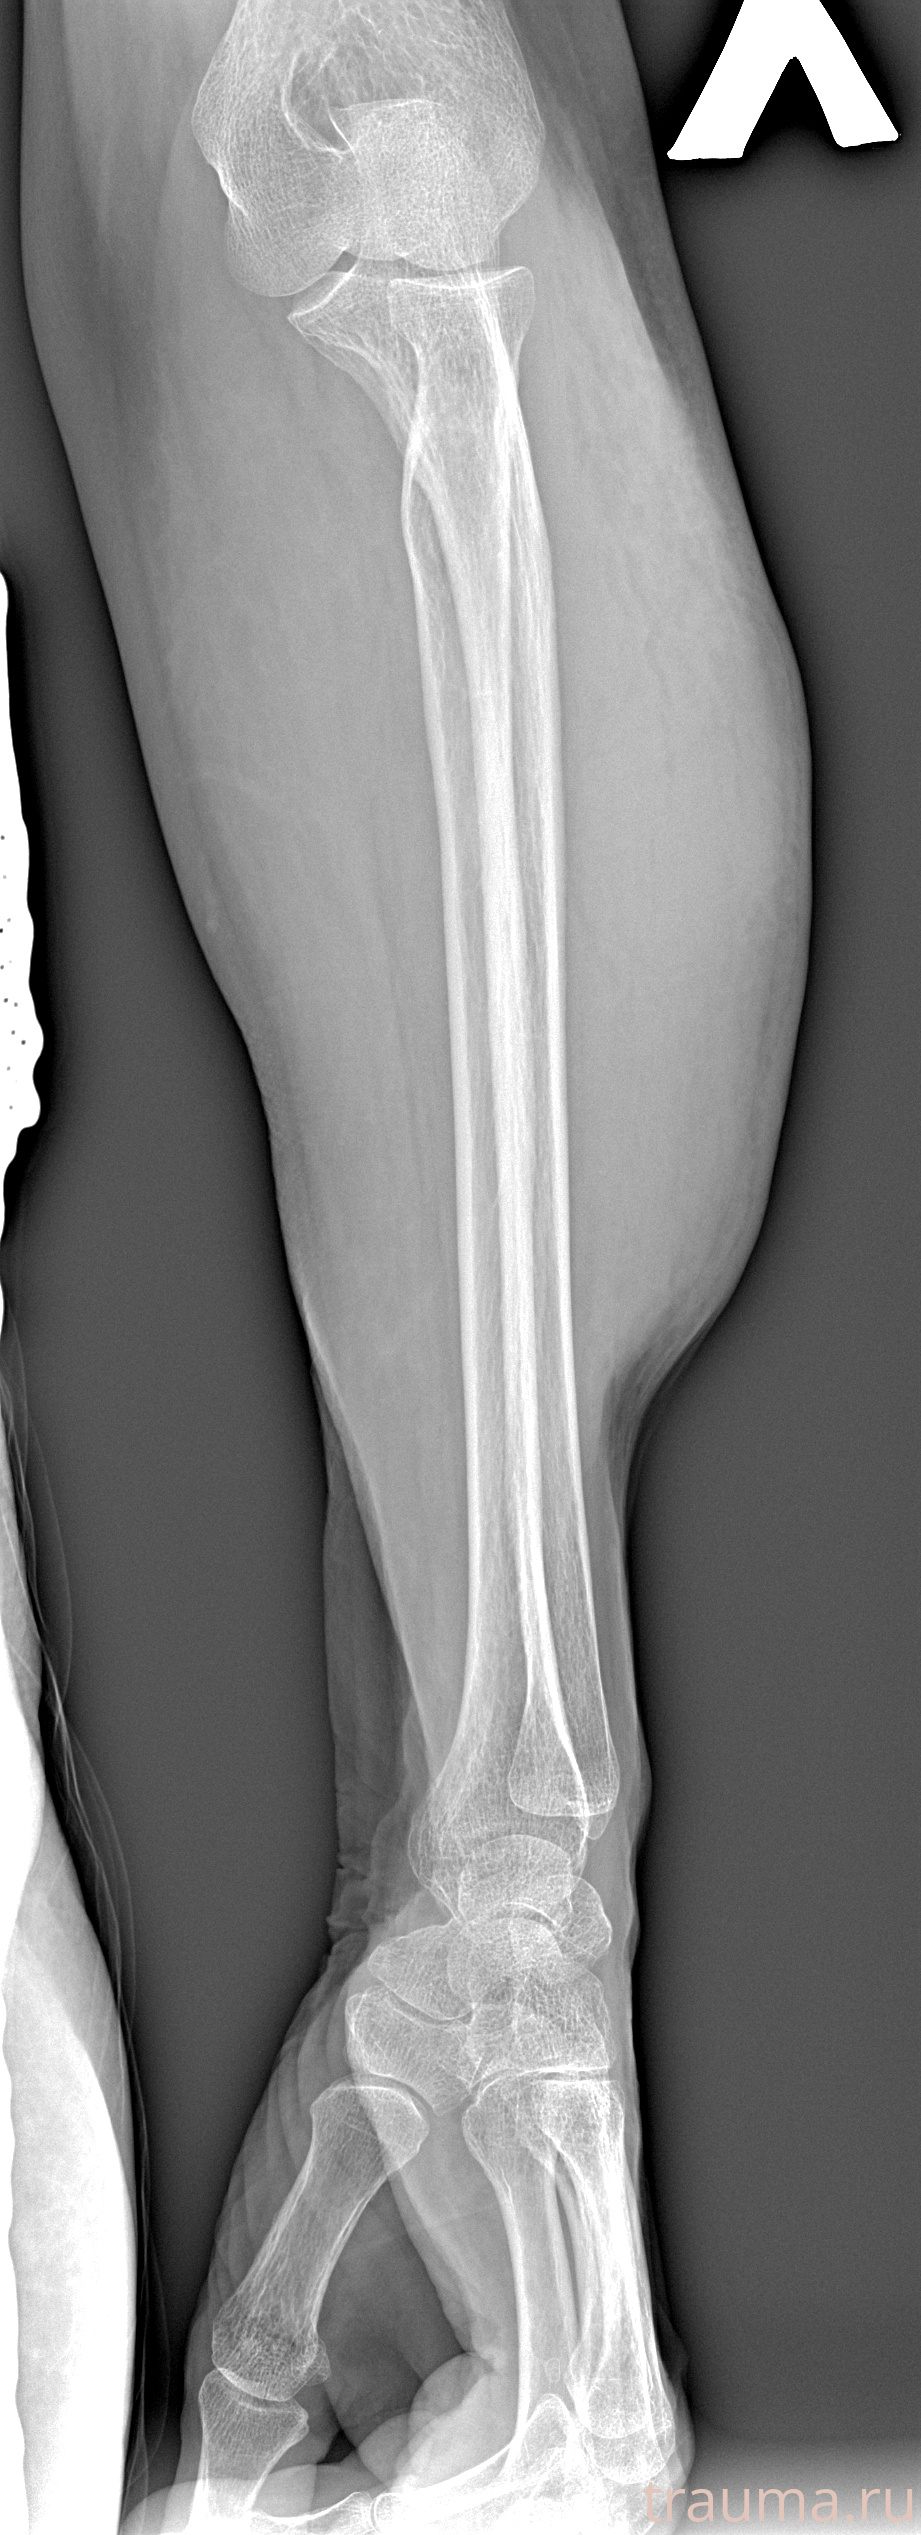

Рентген на дому: по вашему адресу приезжает врач-рентгенолог, травматолог-ортопед с мобильным рентгеновским аппаратом, проводит диагностику травмы или заболевания, делает необходимые рентгенограммы, дает рекомендации по дальнейшему лечению. Получить качественные снимки в домашних условиях возможно благодаря уникальной методике, разработанной МосРентген Центром для института  Склифосовского